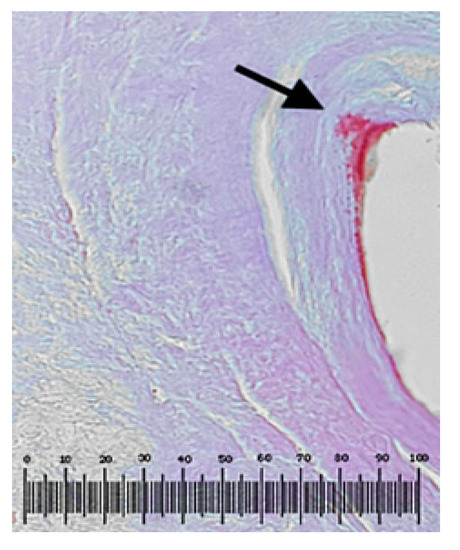

3.3. Evaluation of Tissue/Stents Interface by Histopathological Analysis of Surrounding Tissue